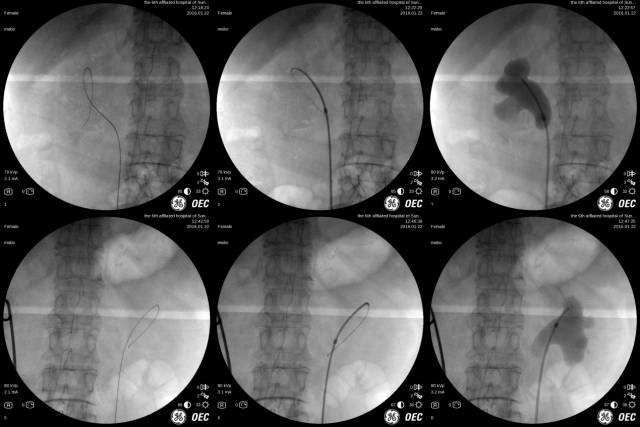

【上图为手术方式,在X线下操作,可术中逆行泌尿系造影,了解外鞘及支架位置,最大可能保证所置入的支架位置良好】

会议由中华医学会广州分会泌尿外科学会常委、泌尿外科主任汪中扬主持,该院泌尿外科马波主治医师带领的博士团队为与会者带来了丰盛的学术大餐。会上直播手术间演示了在X线透视下为因肿瘤压迫导致输尿管梗阻的患者经输尿管置入导管的全过程。术后,马波还以《Resonance™金属双J管的临床应用体会》为题作了精彩报告。